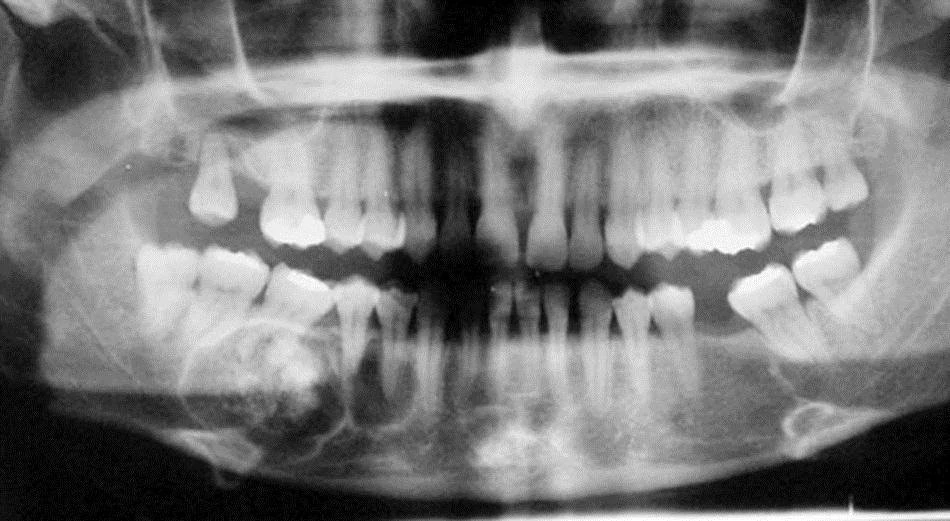

Trước khi phát hiện u răng, bệnh nhân không có triệu chứng lâm sàng nào. Thông qua hình ảnh X-quang, các bác sĩ phát hiện bệnh nhân có 1 khối cản quang tròn ở vùng răng 45, 46 xương hàm dưới bên phải, đường kính 3 cm. Các bác sĩ khoa Răng hàm mặt đã chỉ định phẫu thuật khoét u răng, sau hơn 2 giờ ca phẫu thuật mở xương, đục vát nhằm tránh tổn thương dây thần kinh răng dưới đã lấy ra được nhiều răng nhỏ dị dạng.

Hiện tại, bệnh nhân đã ổn định, chụp X-quang sau phẫu thuật không còn hình ảnh u răng. Kết quả giải phẫu bệnh cho thấy thành phần chủ yếu của u răng là men ngà, tủy và cement.

Hình ảnh chụp X-quang cho thấy bệnh nhân có rất nhiều chiếc răng nhỏ dị dạng. Ảnh: Bệnh viện cung cấp